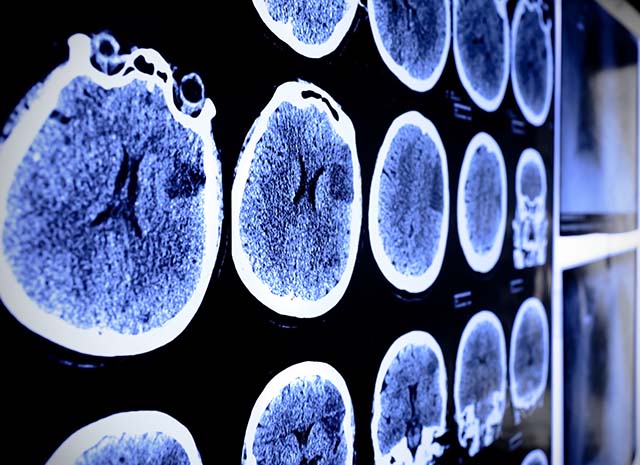

Researchers to investigate possible link between stroke and Covid-19

The Stroke Association has joined forces with the BHF Data Science Centre to investigate any possible links between Covid-19 and life-threatening strokes.

Data analysts will compare stroke in patients who have tested positive for Covid-19 with patients without the virus, to confirm if Covid-19 increases risk of stroke and, if it does, by how much.